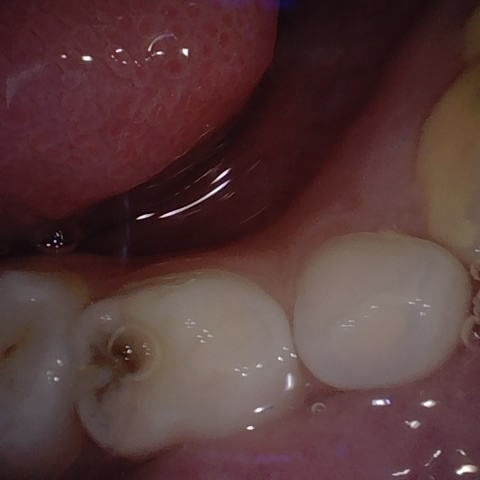

Incorrect Quality Level

The reference annotation for this image is

None

.

Please select the correct quality level.

Annotated as "Good"